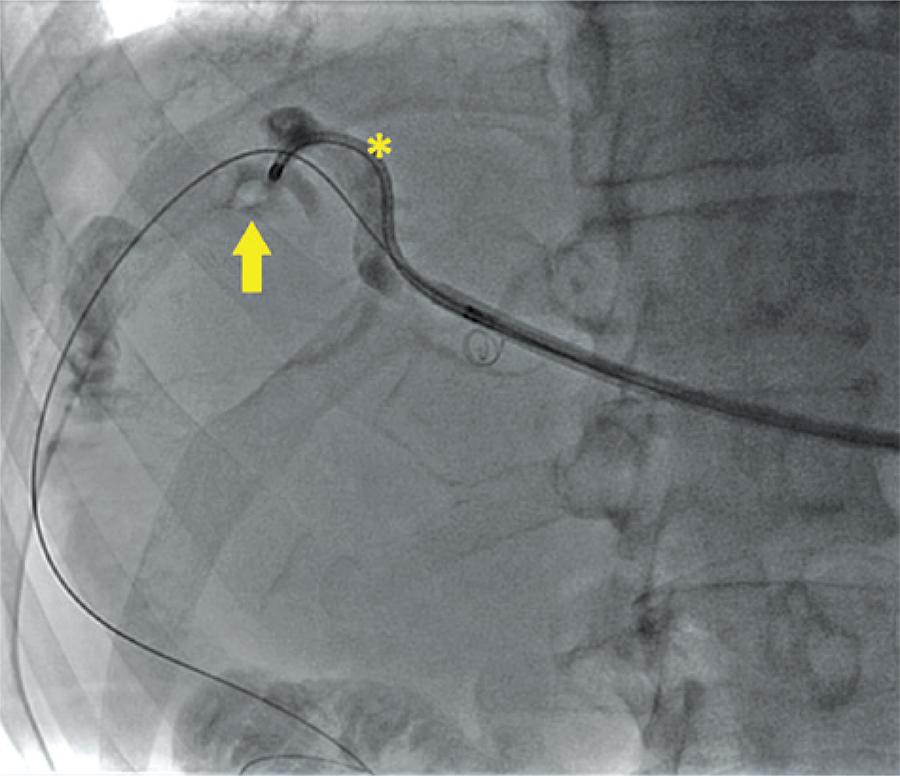

Percutaneous treatment of complex biliary stone disease using endourological technique and literature review

Most biliary stone diseases need to be treated surgically. However, in special cases that traditional biliary tract endoscopic access is not allowed, a multidisciplinary approach using hybrid technique with urologic instrumental constitute a treatment option. We report a case of a patient with complex intrahepatic stones who previously underwent unsuccessful conventional approaches, and who symptoms resolved after treatment with hybrid technique using an endourologic technology. We conducted an extensive literature review until October 2012 of manuscripts indexed in PubMed on the treatment of complex gallstones with hybrid technique. The multidisciplinary approach with hybrid technique using endourologic instrumental represents a safe and effective treatment option for patients with complex biliary stone who cannot conduct treatment with conventional methods.